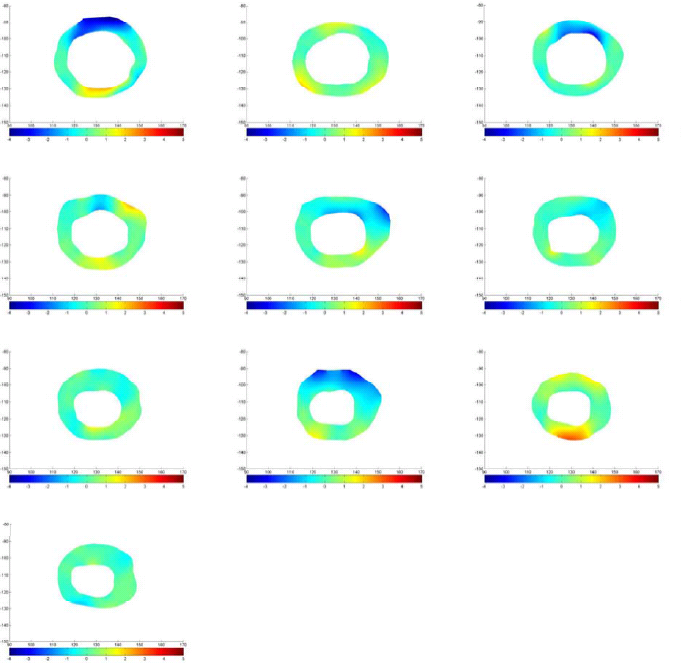

In this research the database provided by the authors of [23] is used. This database contains the MRI images of 33 patients which consists of 7980 two dimensional MRI images from different slices of the heart muscle. Each cardiac cycle is divided into 20 steps. These images are acquired from patients with different types of problems like Cardiomyopathy, Aortic regurgitation, Ischemia and Enlarged ventricles. All of patients were under 18 and the distance between slices is between 6 to 13 millimeters. Each image’s size is and the inner and outer contour of the heart is indicated by hand by the author of [23]. Based on the additional information attached to the database it is known that patient 23 suffers from Myocardial Infarction (MI). Also patients 18 and 25 have normal heart muscle which can be useful in understanding the effects of MI. Here the data from these three patients are used to achieve the results. Fig. 6 displays the cardiac cycle of the patient 23 for the first slice. The inner and outer contours of the left ventricle are determined in the images.

Inner and outer contours in MRI images are determined with hand by [23]. Each contour consists of 32 points. The goal here is to find the one-to-one correspondence between contour points between frames. The resolution of the data points is increased by interpolation. Another thing to consider here is that the deformation of heart muscle is not only a concentric radial deformation, but it also contains rotation. On average, during systole, the cardiac muscle has a 7 degree clockwise rotation which needs to be considered in finding one-to-one correspondence and displacement vectors’ computation. The contour points are then down-sampled to reduce the computational complexity. Fig. 8 displays the displacement vectors of one slice of MRI data for subjects 23 (b) and 18 (a) during systole. The existence of MI has a visible effect on the deformation of cardiac muscle.

Using the displacement vectors, the boundary conditions of the FEM model can be defined. After applying the boundary conditions and then meshing the domain with a fine triangular mesh, FEM is used to solve the governing equation of deformation. The result of FEM is the displacement values in and directions in the deforming body’s domain. Fig.9 shows the results of FEM for two slices of subjects 25 and 23 during systole for horizontal and vertical displacements.

which in 2D case can be simplified because . Using this parameter we are able to monitor the changes in strain maps of heart muscle during deformation. Computing effective strain values for different slices of cardiac muscle, these values are used for comparison between healthy and MI subjects. Fig. 10 represent the results for first slice of healthy subjects, 18 and 25, and MI subject 23 during the cardiac cycle.